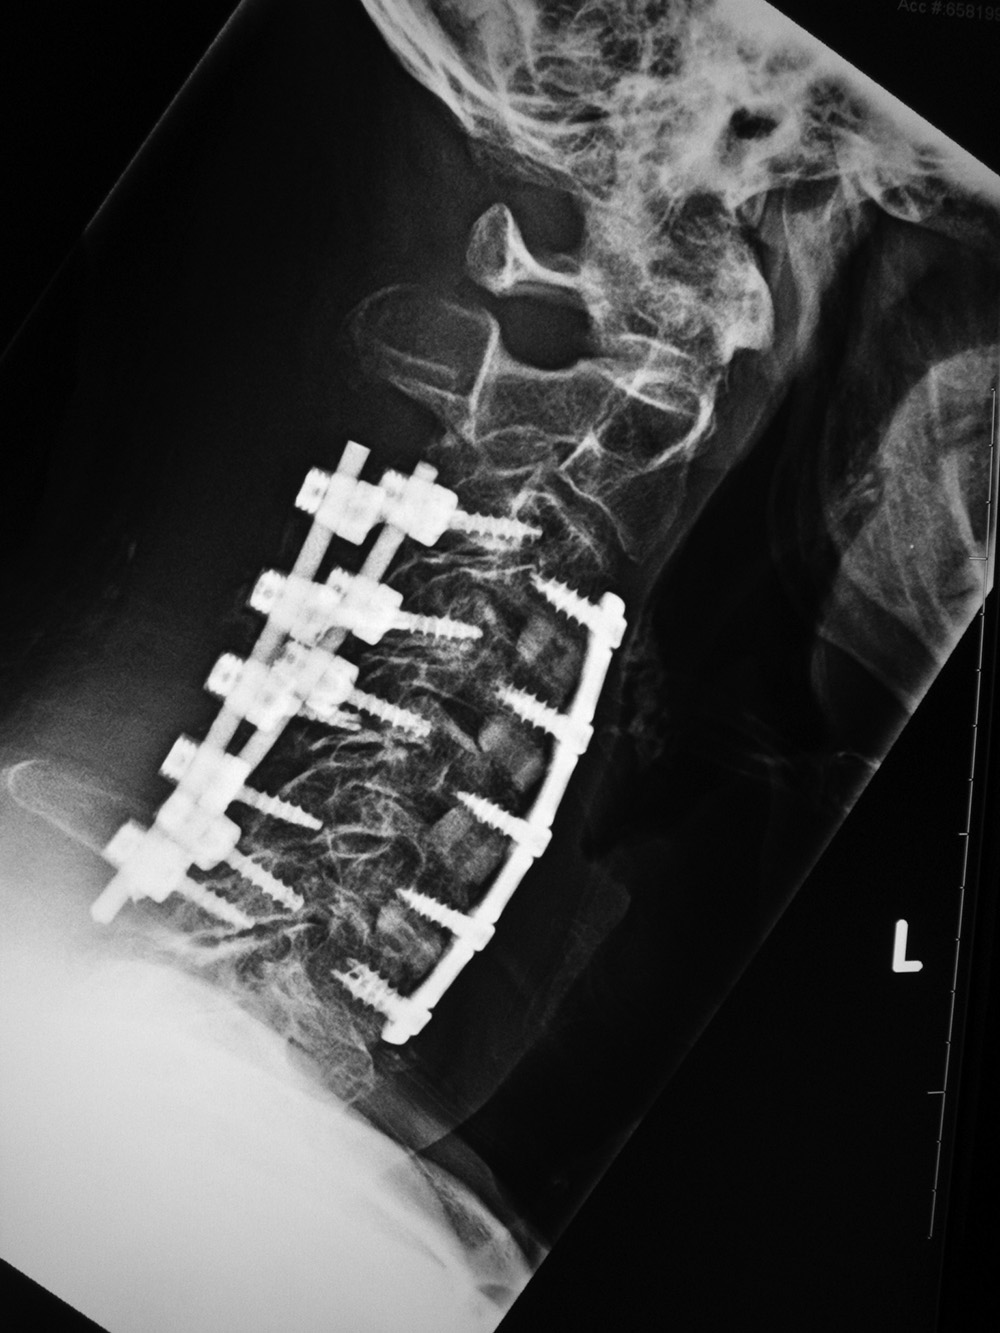

Cervical spine anterior and posterior fusion Cervical spine anterior and posterior fusion with intervertebral bone struts (plugs)

Anterior and posterior cervical spine fusion AP view Anterior and posterior cervical spine fusion lateral view Anterior and cervical spine fusion with intervertebral bone struts Anterior and cervical spine fusion with intervertebral bone struts

Young woman with traumatic locked facets at C6-7 and C7 body fracture. A posterior cervical fusion with lateral mass screws (cervical spine) and pedicle screws (thoracic spine) and rods extends from C4 to T2. There is an anterior cervical fusion plate and screws at C6-7 with a intervertebral disk cage at C6-7 and a crosslink at C6. There is an anterior cervical fusion plate that extends from C3 to C7 and posterior lateral mass screws and rods on each side from C3 to C7. Intervertebral bone struts (plugs) are present at the disk spaces from C3 to C6.